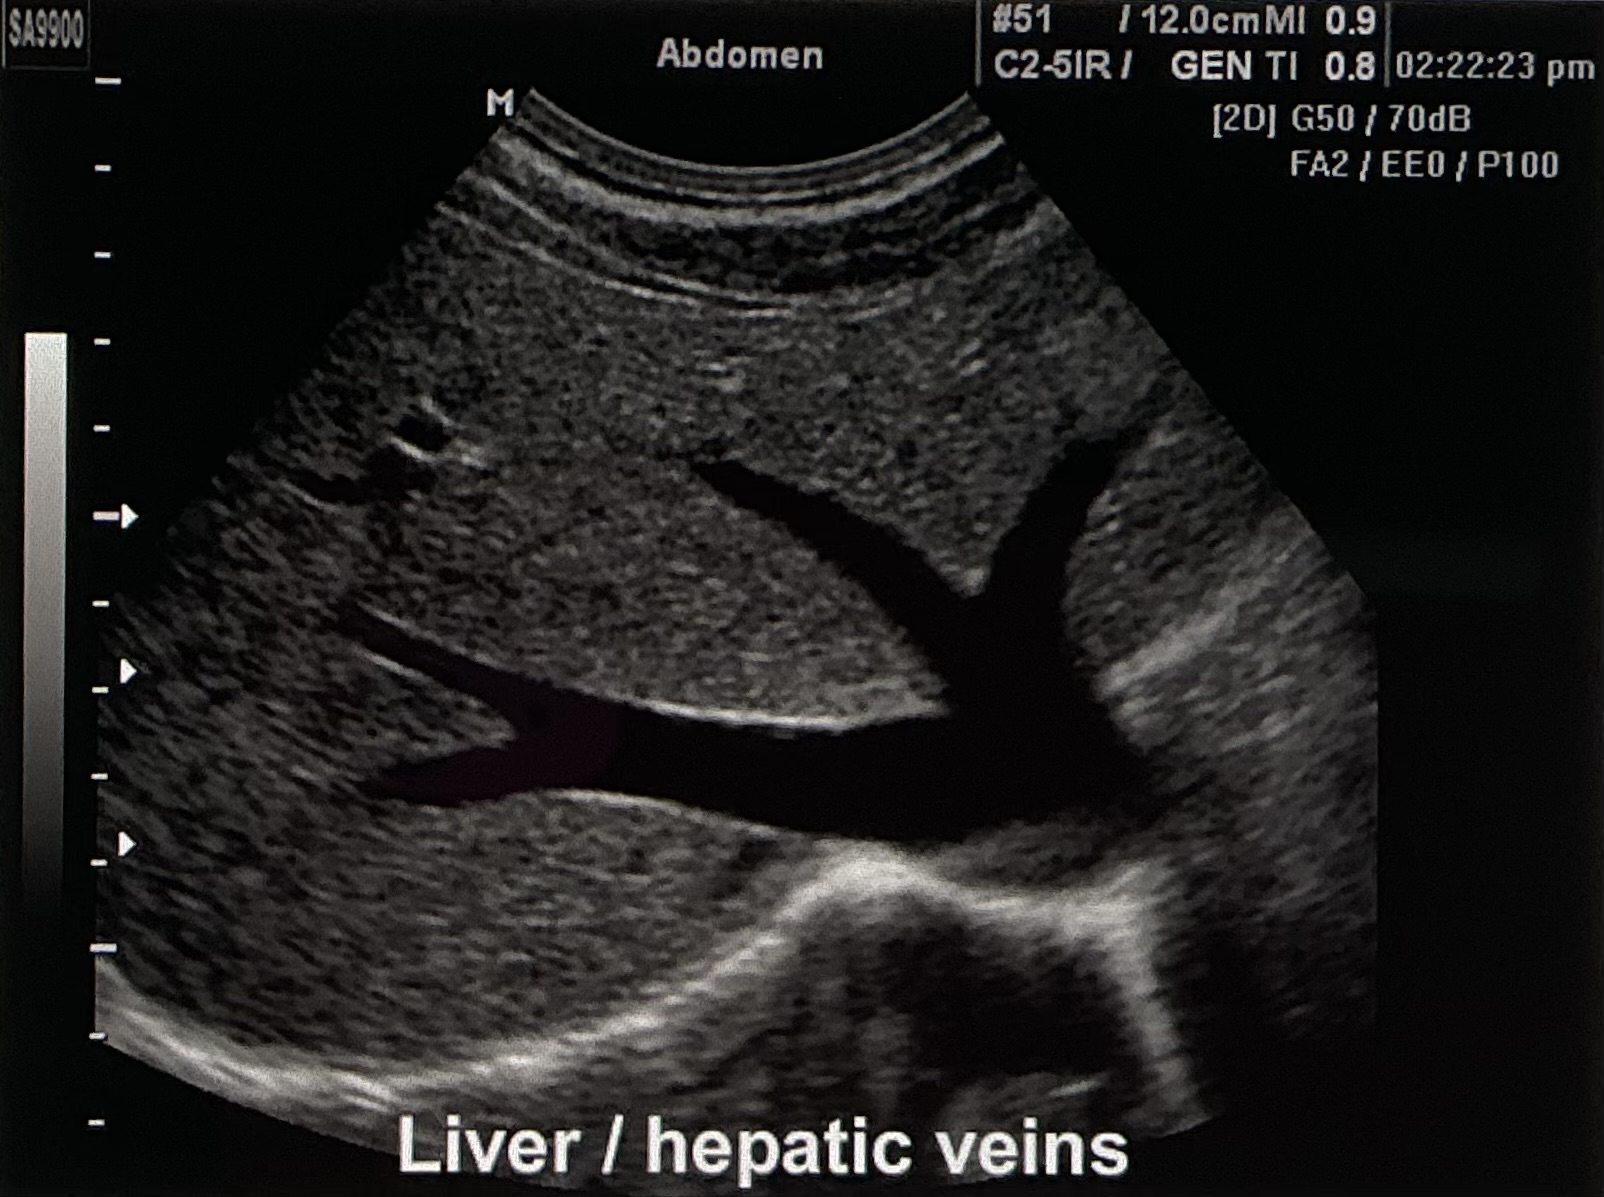

Describe the sonographic appearance of this image.

Left lobe of the liver, specifically the hepatic veins.

The liver tissue appears homogenous and hyperechoic to the vessels. It is bordered by an echogenic line, which is the diaphragm. The hepatic veins appear anechoic throughout, and they are hypoechoic to the surrounding tissue.